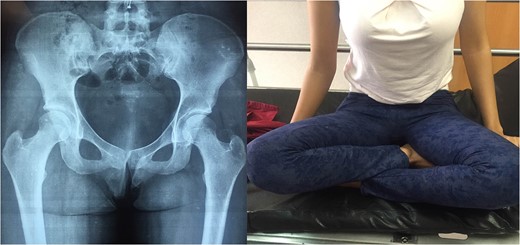

1: Patient with hip flexion and internal rotation and X-ray with traumatic bilateral posterior hip dislocation.

CT-Scan show bilateral posterior hip dislocation without evidence of fracture or articular fragments.